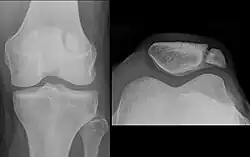

![]() Right knee | |

The upper three-quarters of the patella articulates with the femur and is subdivided into a medial and a lateral facet by a vertical ledge which varies in shape.

In the adult the articular surface is about 12 cm2 (1.9 sq in) and covered by cartilage, which can reach a maximal thickness of 6 mm (0.24 in) in the centre at about 30 years of age. Owing to the great stress on the patellofemoral joint during resisted knee flexion, the articular cartilage of the patella is among the thickest in the human body.

The upper three-quarters of the patella articulates with the femur and is subdivided into a medial and a lateral facet by a vertical ledge which varies in shape. Four main types of articular surface can be distinguished:

- Most commonly the medial articular surface is smaller than the lateral.

- Sometimes both articular surfaces are virtually equal in size.

- Occasionally, the medial surface is hypoplastic or

- the central ledge is only indicated.